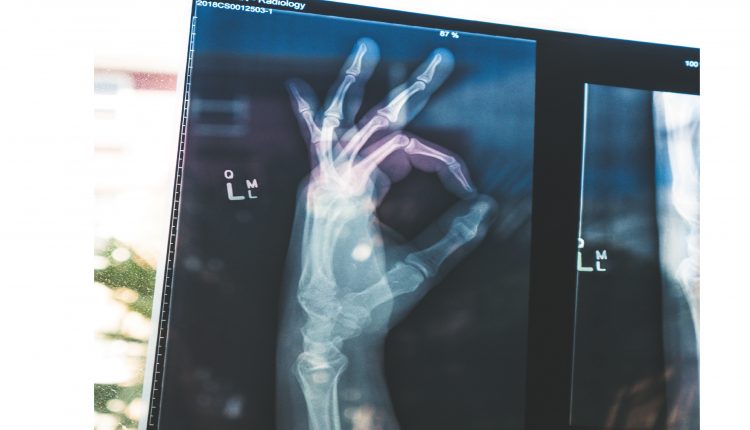

هوش مصنوعی در رادیولوژی

بسیاری معتقدند هوش مصنوعی که گاهی از آن با عنوان یادگیری ماشین نیز نام برده می‌شود، می‌تواند در روندهای کاری رادیولوژی اثرات عمیقی بر جای بگذارد. هوش مصنوعی می‌تواند گردش کار رادیولوژیست‌ها را بهینه کرده، کمی‌سازی را تسهیل کرده و در کشف نشانگرهای ژنومی کمک کند. افزودن اطلاعات حاصل از الگوریتم‌های هوش مصنوعی به گزارش‌ها و گردش کار، می‌تواند مراقبت از بیمار را به میزان چشمگیری بهبود بخشد. همچنین امکان کاهش زمان انتظار برای بیماران اورژانسی و قابلیت رادیولوژی از راه دور را فراهم می‌کند.

یک ویژگی جذاب رادیولوژی، وجود مجموعه‌های بزرگ داده است. زمانی که در حوزه‌ی خدمات سلامت از داده صحبت می‌شود، منظور بیماران منحصربه‌فرد است. رادیوگرافی‌ها، سی‌تی اسکن و سونوگرافی آنها همگی در دسترس هستند. هر بار که بیمار به بیمارستان مراجعه می‌کند، رادیوگرافی قفسه سینه یا ماموگرافی که قبلا انجام داده برای انجام مقایسه در اهداف تشخیصی، در اختیار رادیولوژیست است. آنچه رادیولوژی را بسیار جذاب کرده، وجود داده‌های عینی است. تصاویری که همیشه در دسترس خواهند بود. جنبه‌ی تسهیل جمع‌آوری داده و امکان استفاده از آن در پرونده‌ی پزشکی بیمار، باعث جلب توجه ها به رادیولوژی شده است.